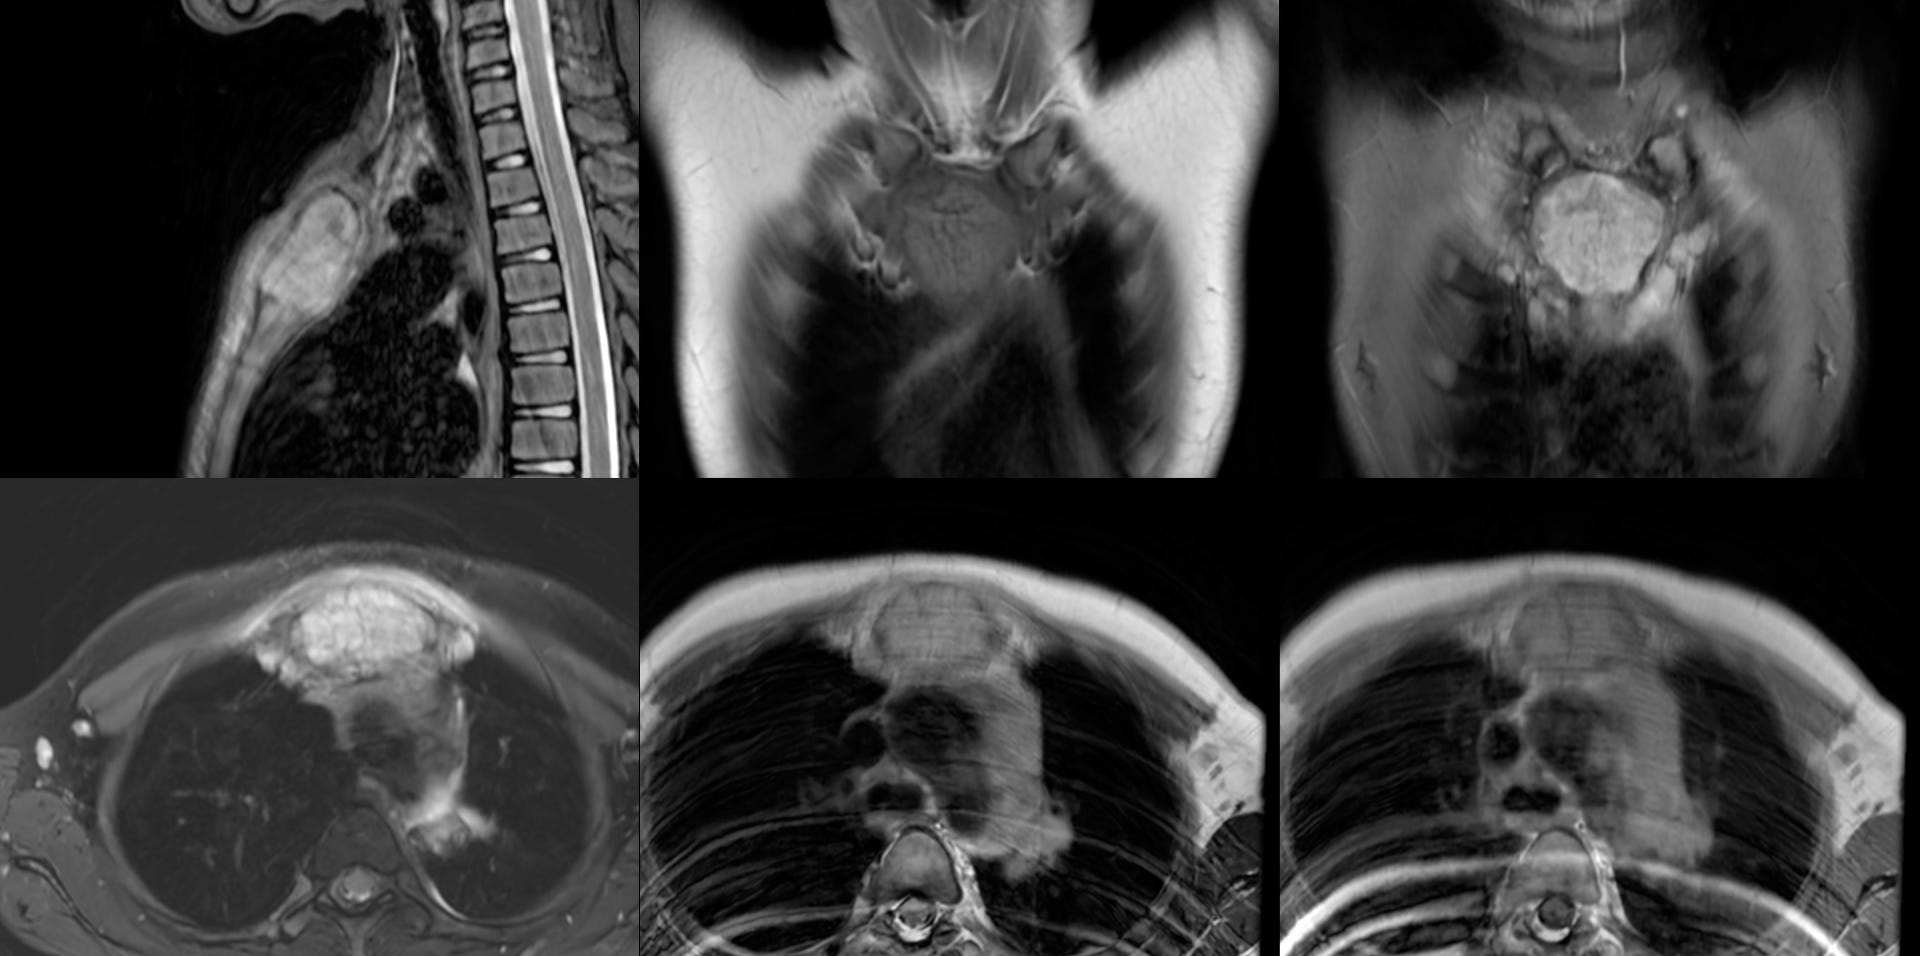

MRI showed an expansile osteolytic lesion in the manubrium sternum.

There were also enlarged left supraclavicular and mediastinal nodes.

The patient was referred for a CT guided biopsy. On CT, the lesion had a “bone-in-bone” appearance.